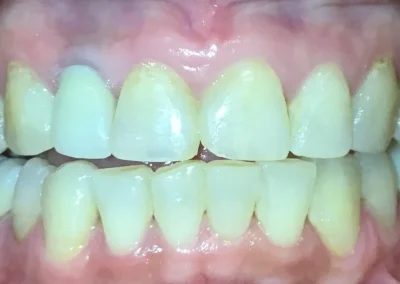

Esthetic Crowns

Esthetic Crowns Before and After